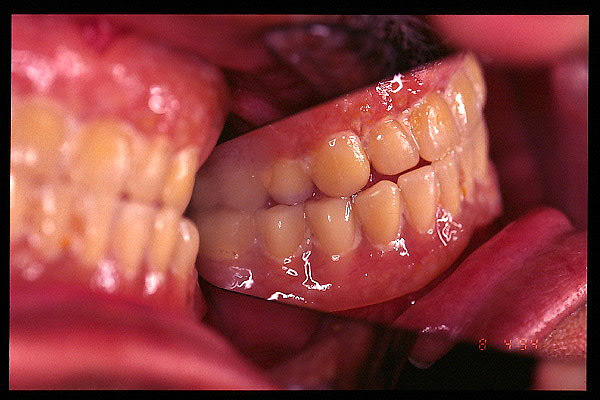

CM Falta de contactos interoclusales